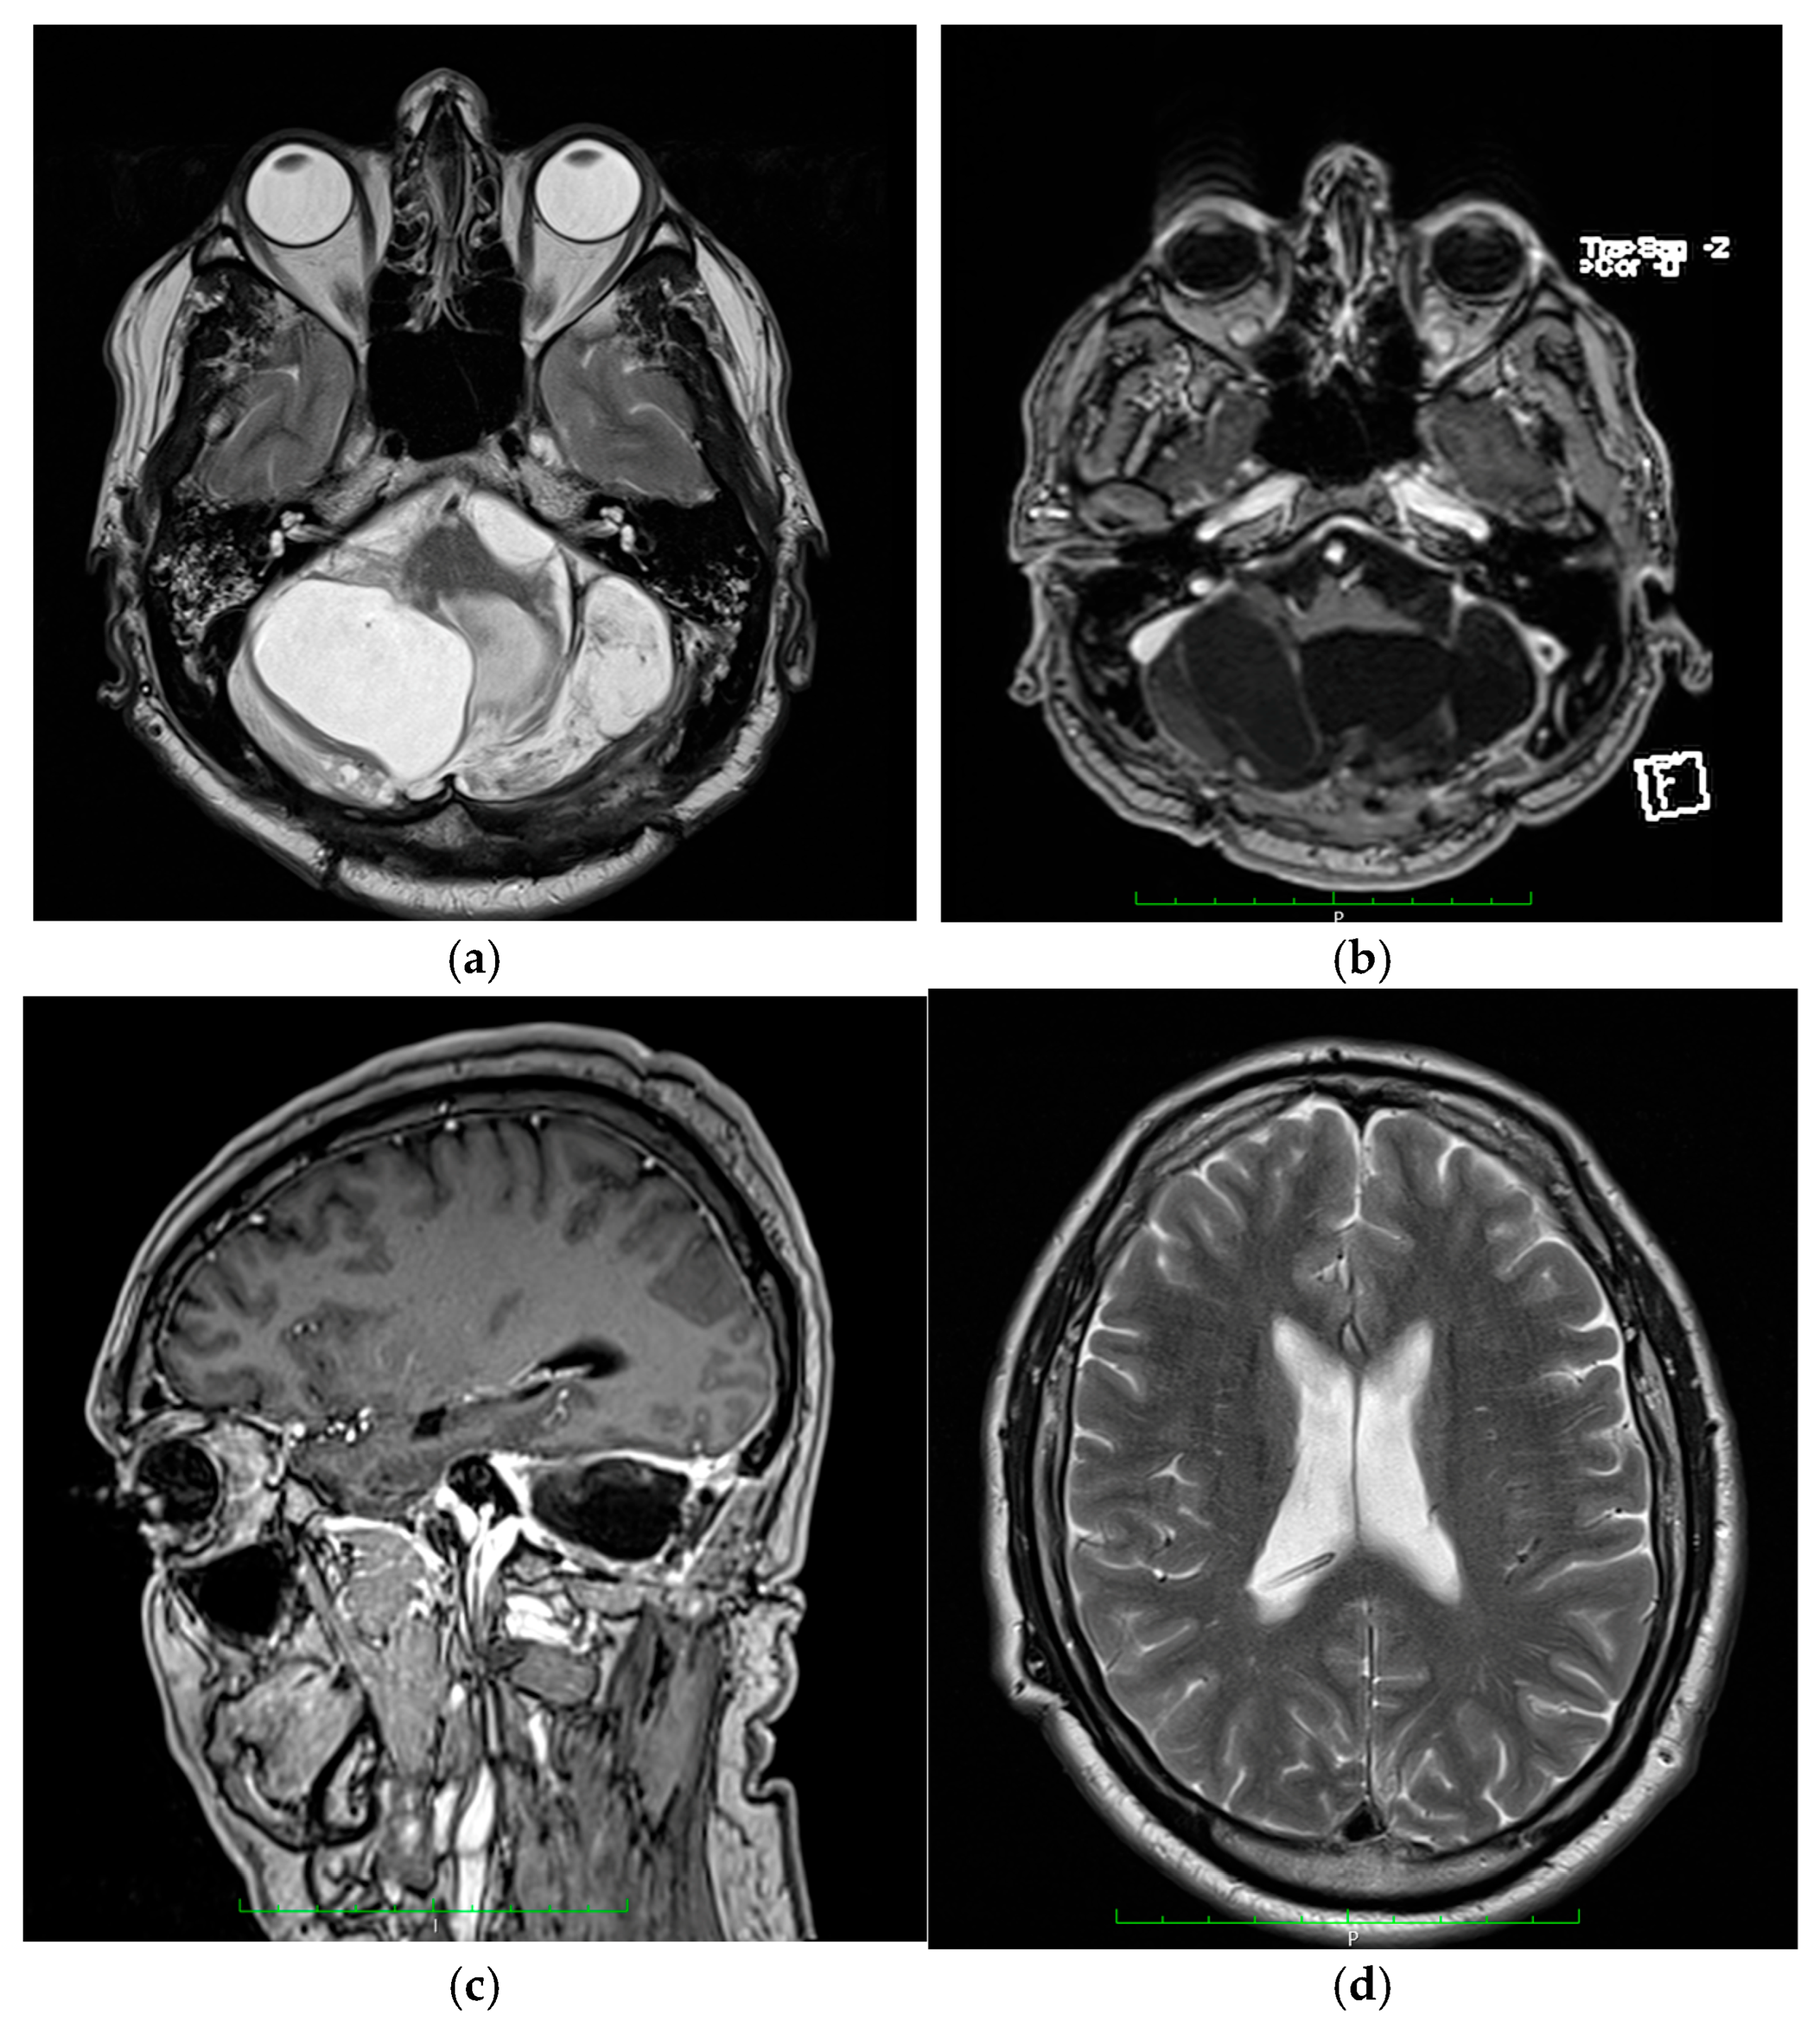

3.1.1. Patient One